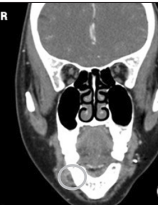

口内检查发现患者右下颌前磨牙颊侧前庭处可见一肿胀,约2*1.5cm大小,质韧,扪诊无疼痛。颈部及颌下淋巴结未见肿大。 全景片未见明显异常。 CT显示右下颌第一前磨牙处有一约2cm大小低密度肿块

由于肿块靠近颏孔,术中需要精细解剖,以确保最小的神经损伤。